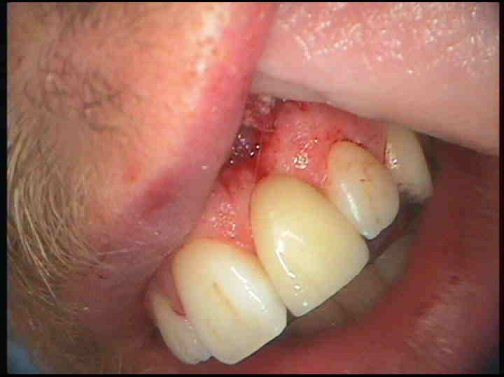

About a month after the extraction of my front tooth I noticed a big change in my health. I had a lot more energy than I used to, and when I did too much, it wasn't still effecting me days and days later. I clearly had found a large source of infection in my jaw. But this infection had been there for over a decade already, and had never been enough to bring down my health before. With my new energy I was able to take on more work, and I spent quite a lot of time my time helping my Dad on the farm, which is something I really enjoy doing. About 3 months later thought my health again started to deteriorate. The pain I was getting in the lymph nodes on the left side of my neck was getting really bad and my underarms were swelling up and the skin was pealing off. I immediately knew that I must have had an infection around my wisdom tooth, regardless of the advice the dentist had given me, so I set upon a quest to get that tooth removed. This proved to be a lot harder than I thought because most dentist won't touch horizontally impacted wisdom teeth. The dentist that had removed my front tooth, couldn't do it, but she kindly gave me a copy of my own x-ray, which is something my local dentist refused to do. It showed I had this problem.

The shadow area under the tooth is literally where infection has destroyed the bone. How my local dentist could think this is fine, I've no idea. The dentist that extracted my front tooth referred me to a dentist in Bristol, that she thought could extract my wisdom teeth. This dentist in Bristol had a unique perspective on dental problems as he had developed cavitations from poor extraction of his wisdom teeth, but also had a root canal next to the site of one of the cavitations. The infection in that area of his jaw had eaten a channel through his jawbone, almost killing him. One of his dentist friends did the surgery on him. Due to insurance reasons he couldn't operate on me though, which was just as well as I couldn't take someone seriously that tried to cast evil spirits out of me, even if he was genuine. (He opened the window to let them out.) I finally found a maxillofacial surgeon locally that I trusted enough to opperate on me. He told me he had stopped counting the number of wisdom teeth extractions he had done when he got to 10,000. I asked him if he had ever heard of cavitations, and he hadn't. So I printed just about everything on the subject I could find on it and asked him to read it. He did. He was pretty shocked at what he read and happily went along with the changes I suggested, which was to remove the peridontal ligaments and thoroughly clean the socket. When I had the surgery, he removed the tooth and found quite a lot of mushy infected bone under the tooth. He cut it out and showed it to me. He did his best to clean the socket, scrape out the ligaments and stitched me up. Because I didn't have much gum around that wisdom tooth I was left with an open hole, for virtually 4 months. The dentist packed it with a sort of wool packed with oil of cloves. A month or two after surger, again I noticed a difference in my health. This time it was a big difference, for the first time in literally years, my sore throat went, no more swelling in my underarms. My health had really returned to me, it was fantastic. When the hole finally healed up, I got my other horizontally impacted wisdom tooth removed. For a while, everything seemed good.